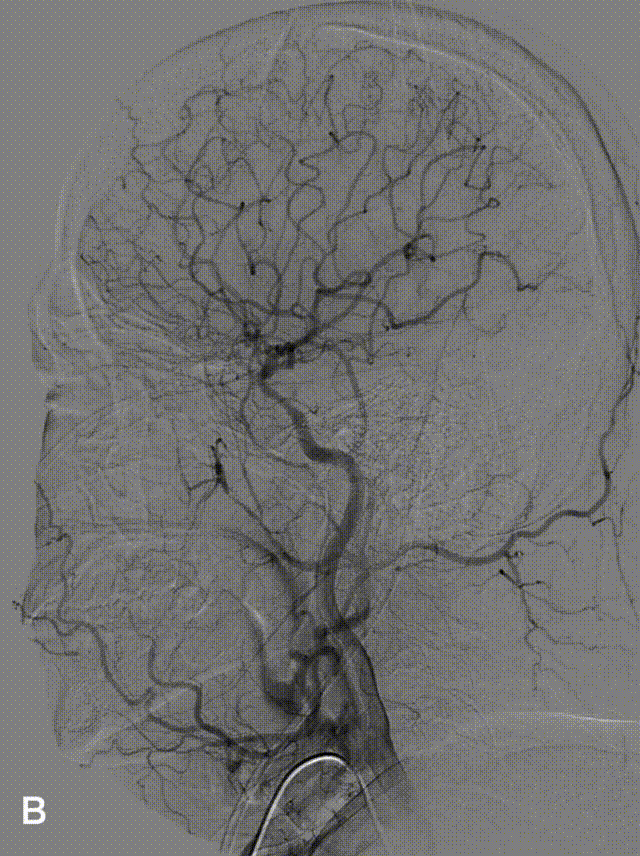

常规消毒、铺巾,全身麻醉,右侧远端桡动脉置入6F动脉鞘,全身肝素化;桡动脉造影显示桡动脉管径平直(图1.A);主动脉弓造影提示I型弓(图1.B)。

图1(A-B)

将SimmonsII导管利用降主动脉成袢行右侧颈内动脉造影(图2.A-B);左侧颈内动脉造影提示左侧颈外动脉通过眼动脉逆流至左侧颈内动脉末端(图2.C-D)。

图2(A-B-C-D)